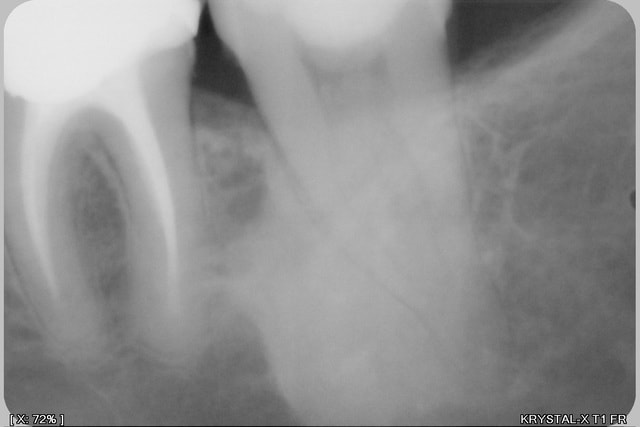

nature osseuse ou cémentaire mais ça ne change rien à l'histoire.

c'est sans conséquence directe, ça se traite pas.

on voit bien l'existence d'un LAD donc ta dentas n'est pas ankylosée mais l'apex sera bien ancré d'après sa forme.

la lésion en tant que telle ne se traite pas. tu peux avoir une ostéite plus facilement car ça doit être hypovascularisée.